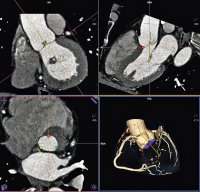

Abbildung 1:

syngo

.CT Cardiac Function-Valve Pilot